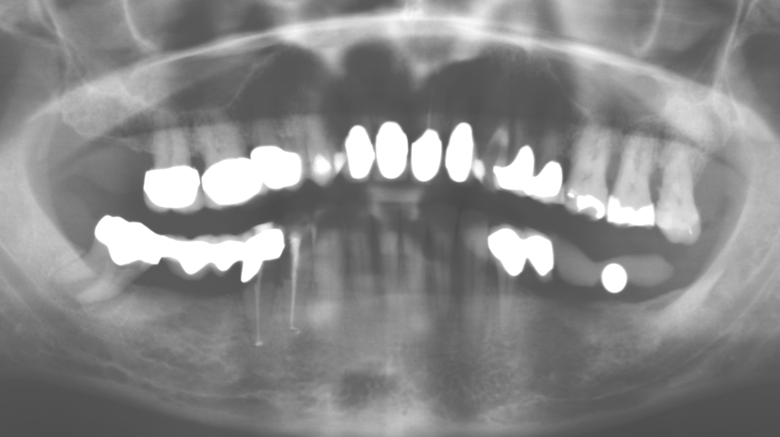

Fig. 1: Radiografia panoramica della situazione iniziale nel Panoramic radiograph of initial situation in 2004.

Fig. 1: Radiografia panoramica della situazione iniziale nel 2004.

Un paziente di 52 anni si è presentato nella nostra clinica per la prima volta nel 2004 a seguito della perdita dei denti nel terzo quadrante, esprimendo il desiderio di un nuovo restauro protesico. La diagnostica parodontale e radiologica ha rivelato la necessità di un ampio trattamento parodontologico. Inoltre, ai denti 48, 28 e 27 è stata attribuita una prognosi molto scarsa e sono stati successivamente estratti (Fig. 1). A seguito del trattamento periodontologico sistematico completato con successo, è stato inserito una protesi dentale fissa con l'inserimento di cinque impianti nelle regioni dentali 35, 36, 37, 46 e 47. Il trattamento protesico dei denti naturali è stato effettuato con corone rivestite in ceramica di biossido di zirconio; gli impianti two-piece composti da abutment singoli in biossido di zirconio e corone similmente rivestite in ceramica di biossido di zirconio (base Cercon colorata, Dentsply Sirona Lab). L'inserimento definitivo del restauro protesico è avvenuto nel 2005.